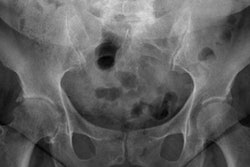

In a new study, researchers from the U.K. examined the x-ray images of 630 obese patients with a body mass index of up to 50 who had previously undergone weight-reducing procedures. They found that the x-ray radiation dose used to acquire images of these patients was markedly higher than the dose used for individuals of average weight. This increase in radiation exposure consequently increased the obese patients' risk of cancer by more than 153%, compared with individuals who received the standard radiation dose.